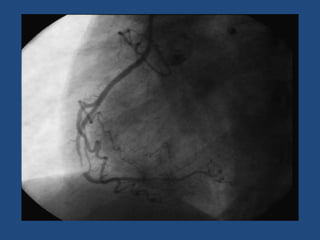

5 semanas después

A los 2 meses